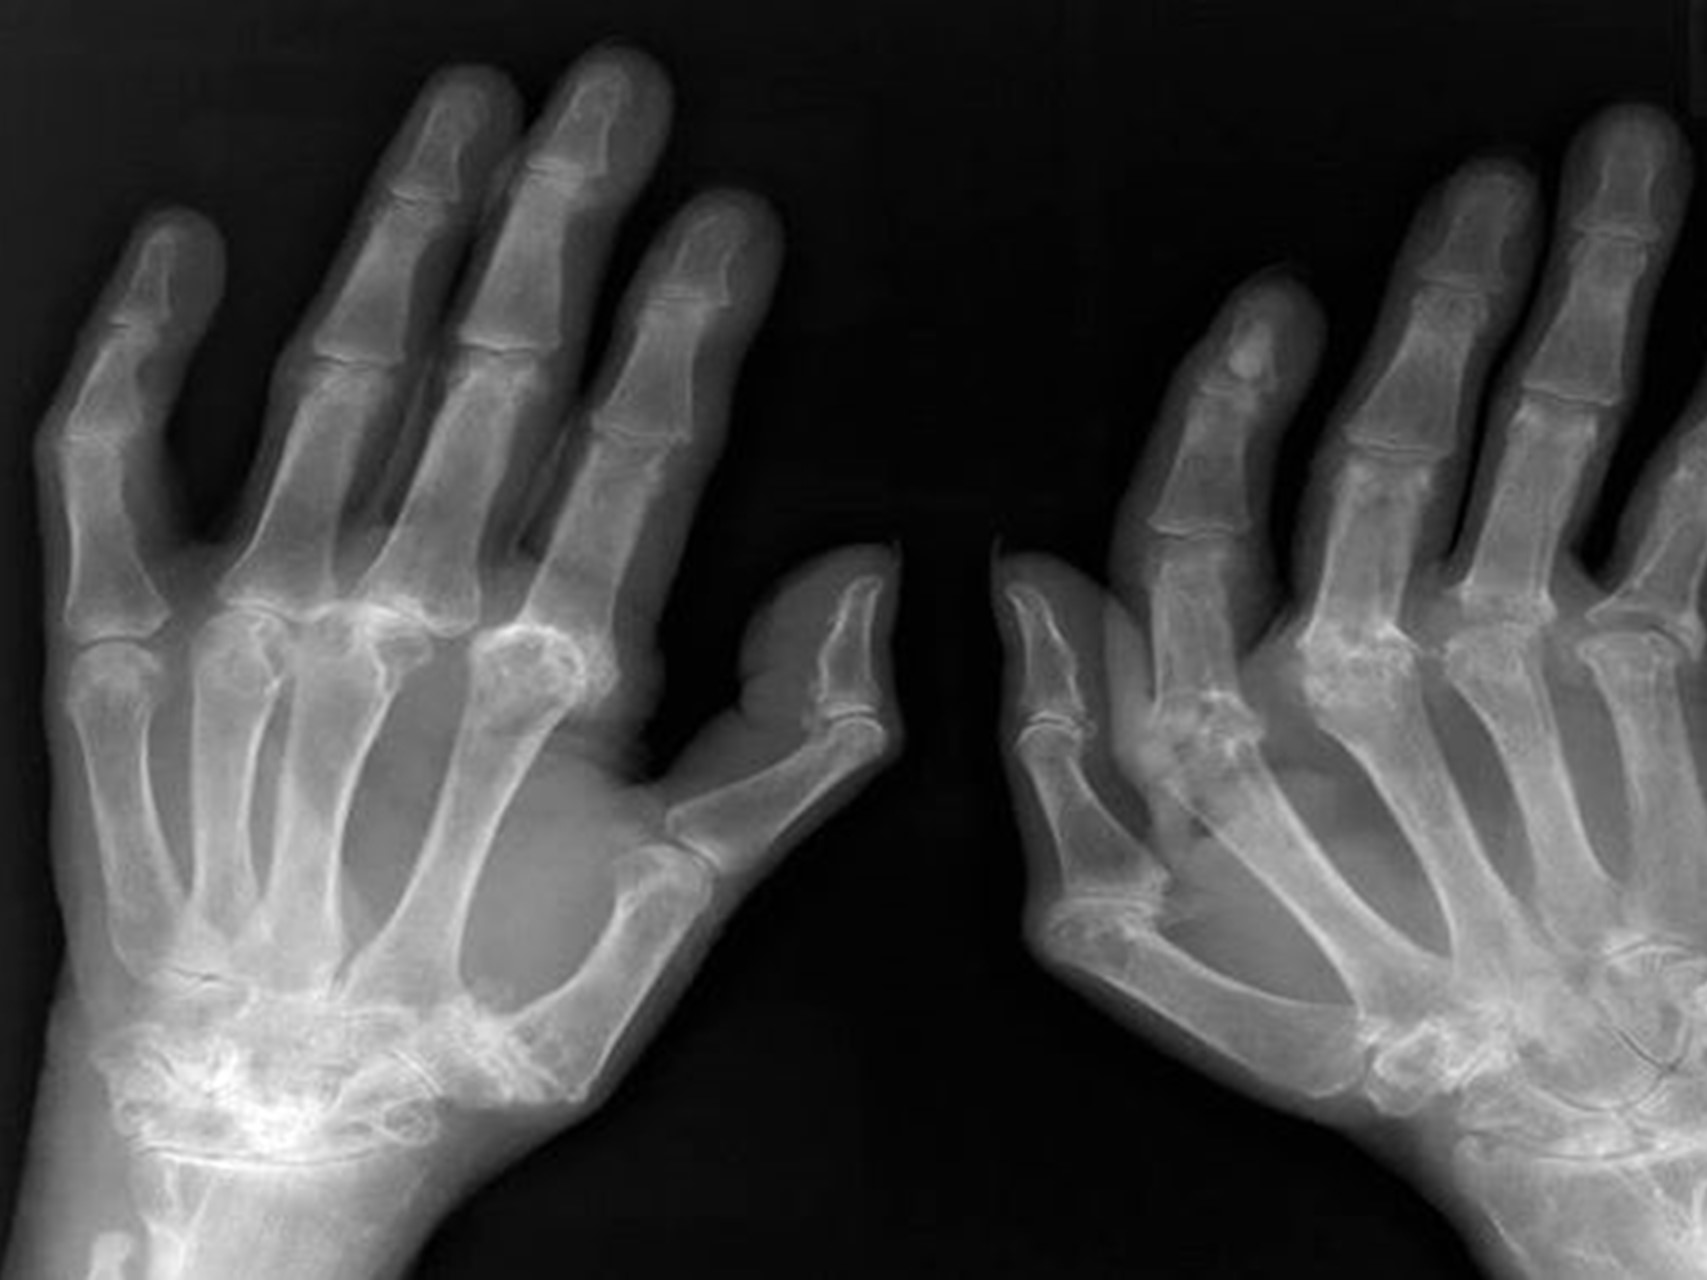

U prvom članku, kao dio farmakokinetičke studije nakon financiranja od strane UCB Pharma, istraživači su proučavali trudnice s ≥ 30 tjedana trudnoće u Francuskoj, Švicarskoj, Nizozemskoj i Sjedinjenim Državama. [1] Ove su žene primale certolizumab, antitumorski faktor nekroze (TNF) za kliničko liječenje različitih bolesti, uključujući reumatoidni artritis, spondiloartritis, psorijatični artritis i Crohnovu bolest. Isključene su žene s abnormalnostima povezanim s trudnoćom preko ultrazvučnih ili laboratorijskih testova, kroničnom ili akutnom placentarnom insuficijencijom ili prethodnom uporabom drugih anti-TNF agensa koji imaju snažan rizik za teratogenost.